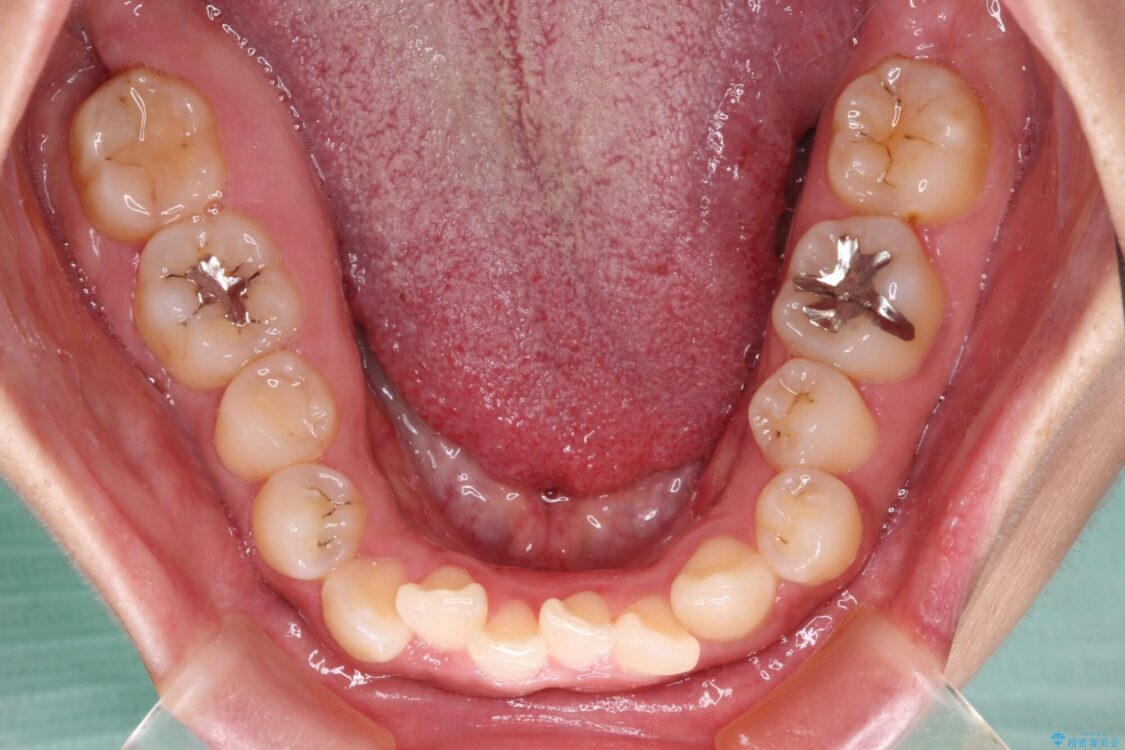

前歯の叢生と八重歯を気にして来院された患者様です。

治療前

• 【モニター】カリエール・ディスタライザーを併用した八重歯のインビザライン矯正 治療前画像